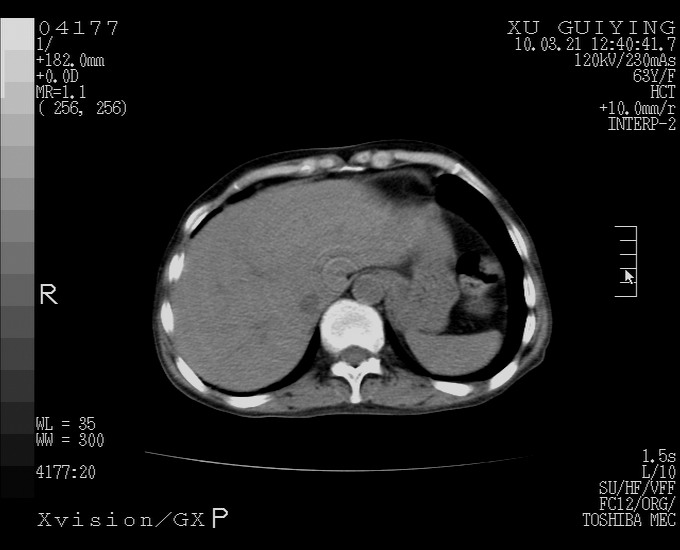

怎么没有增强呢?胆囊那么大,密度有些高啊。

慢性胆囊炎,胆囊占位不排除,建议增强或彩超。

考虑胆囊炎 不除外泥沙样结石

胆囊体积增大,胃窦壁增厚

胆囊体积增大

胆囊体积增大,密度不均匀,结石不除外;胃壁增厚,考虑胃癌,建议增强。

胆囊体积增大 ,建议超声检查。

胆囊体积增大,密度增高,较均匀,外缘也较光滑,应考虑胆囊炎。因为胃未充盈,不好说壁增厚。肝左叶及脾门处见低密度灶,有可能是血管瘤,不排除囊肿。建议超声检查或强化。

胆囊增大,原因待查。

这就是江湖人称的“内科黄疸”, 肝内胆汁淤积症(ic)?